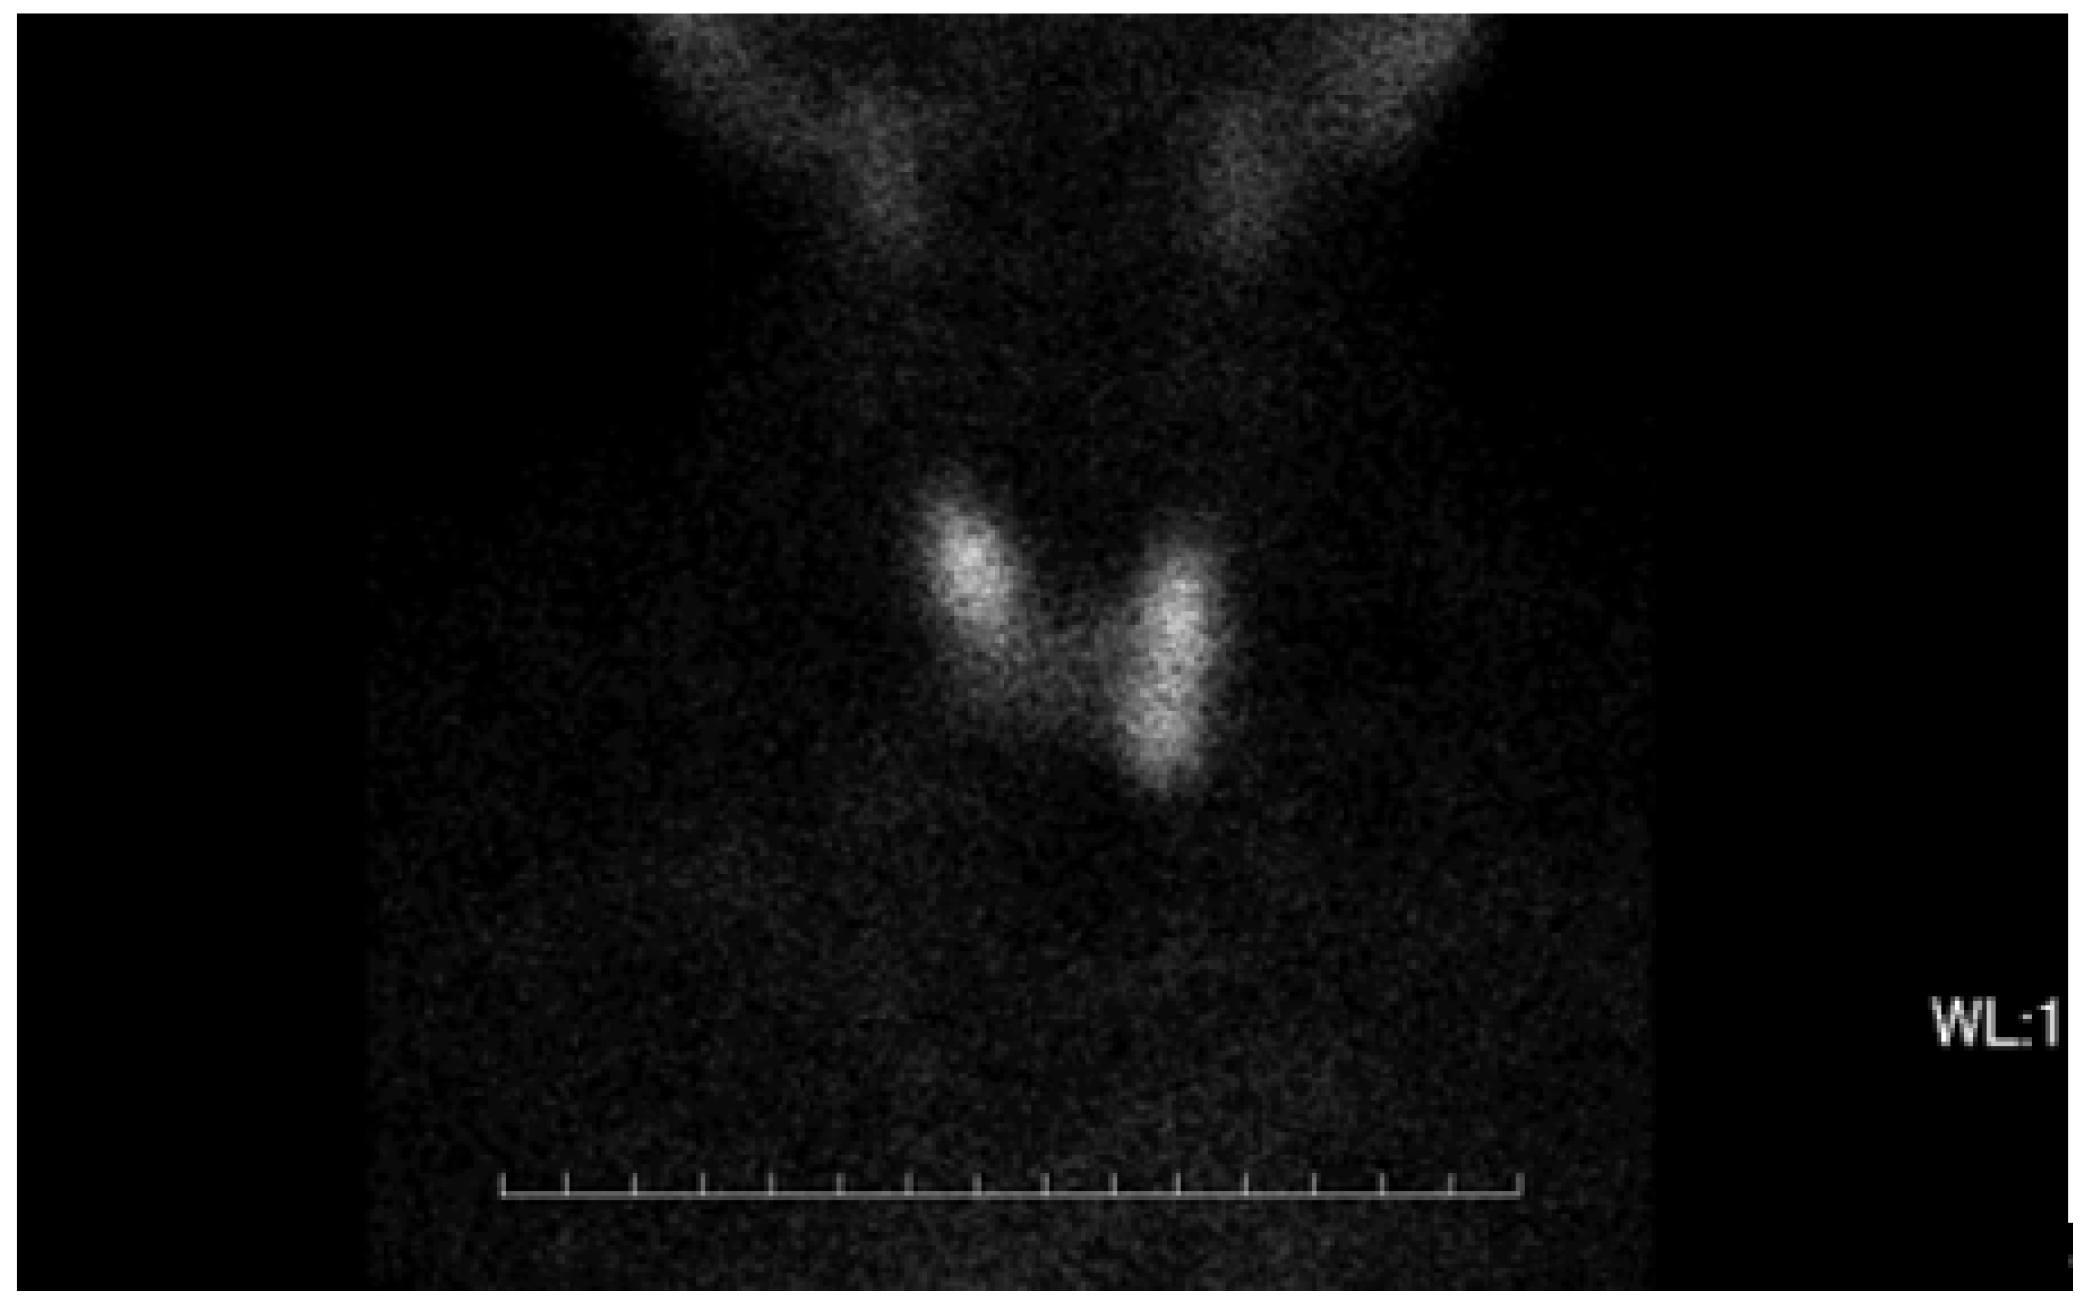

3. Case Report